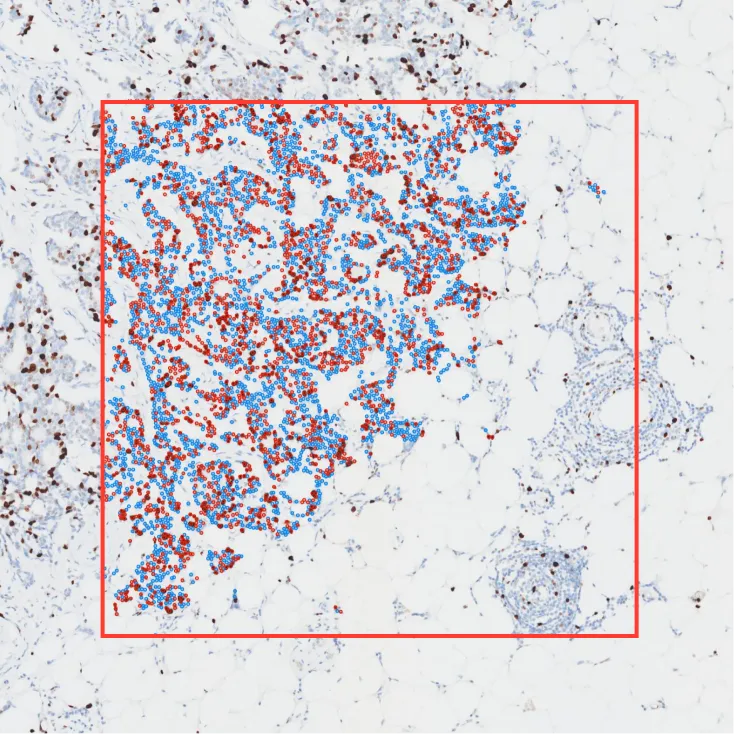

Rectangle